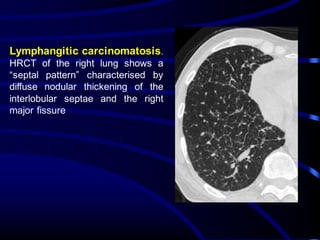

Lymphangitic carcinomatosis.

HRCT of the right lung shows a

“septal pattern” characterised by

diffuse nodular thickening of the

interlobular septae and the right

major fissure